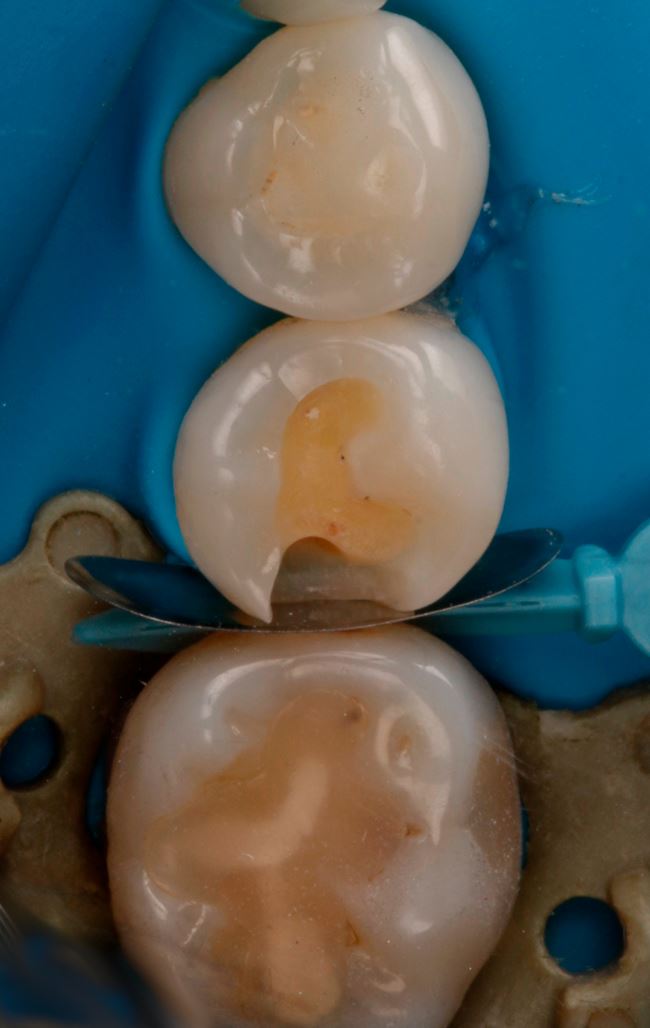

Ubytek na powierzchni dystalnej okazuje się całkiem duży, obejmuje znaczną część zębiny. Teraz nie ma już wątpliwości, że bez wypełnienia się nie obejdzie, a więc podajemy znieczulenie, zakładamy koferdam (ryc. 7) i przystępujemy do opracowania. Po usunięciu amalgamatu w dystalnej części ubytku widać ciemniejszą zębinę (ryc. 8). Usuwamy dystalną listewkę szkliwa i już widać wyraźne odwapnienie (ryc. 9). Dalej jest tylko ciemniej i głębiej (ryc. 10 i 11).

Ryc. 9. Ząb 45 po częściowym otwarciu ubytku.

Ryc. 10. Ząb 45 z częściowo opracowanym ubytkiem próchnicowym kl. II D.

Ryc. 11. Ząb 45 po opracowaniu ubytku kl. II D.